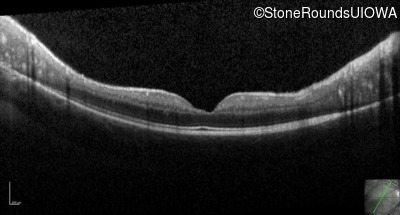

Optical Coherence Tomography - Right - 20/50

Exemplar / OCT Stack